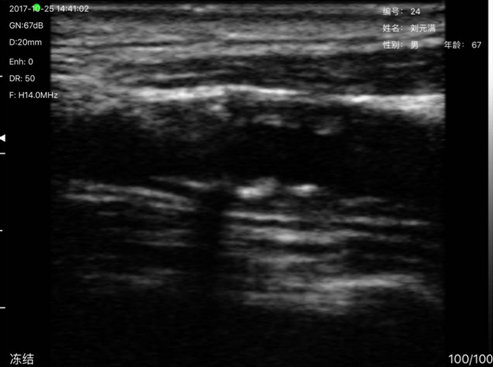

病例1病人刘x满,男,67岁,该病人原来一直反馈头晕,到我所就诊多次,由于缺乏检验设备一直检查不出原因,也未到大医院进行检查,本次有了设备后发现其颈动脉有异常,其到沙县医院复诊后确诊为颈动脉粥样硬化斑块。